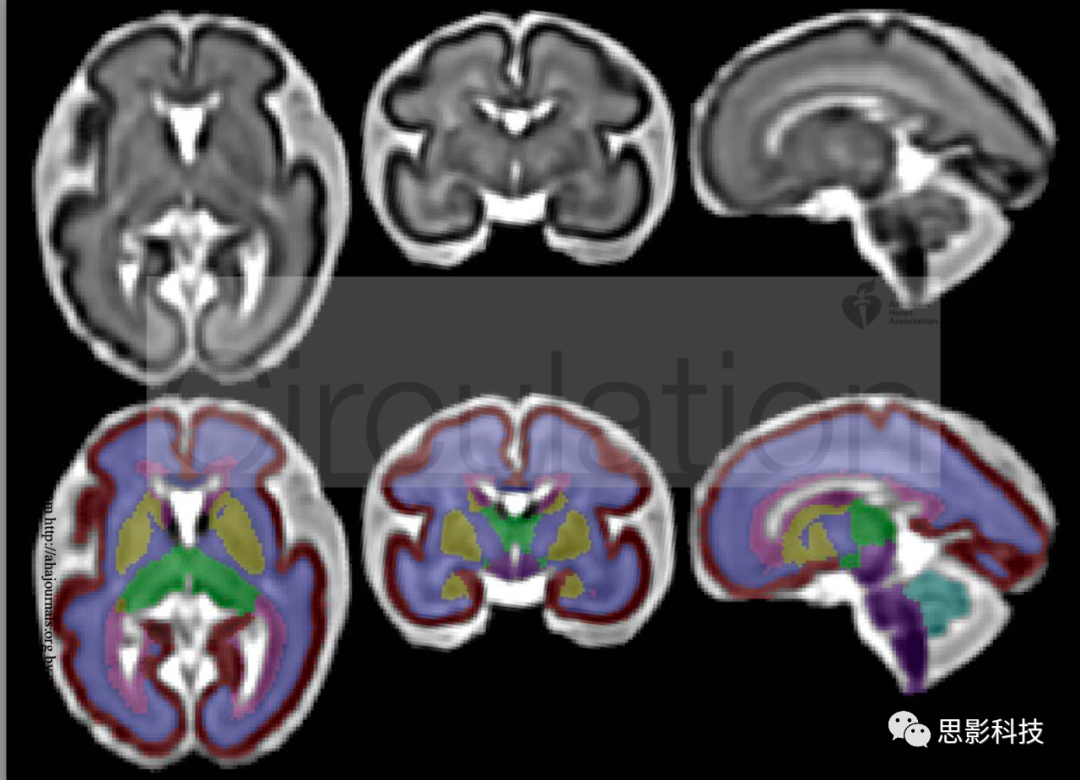

雖然縱向研究包括多個胎兒腦MRI,但本研究分析了胎兒腦MRI的首次掃描數(shù)據(jù)。我們通過3-T西門子MRI掃描儀獲取了多平面重復T2加權單激發(fā)快速自旋回波序列,并使用超分辨率體積重建和基于圖譜的半自動分割軟件處理圖像,以計算區(qū)域和全腦體積;細節(jié)如前所述(1)。全腦體積包括所有腦實質,并排除腦脊液。檢查了15例磁共振成像。

注解  圖1:28周時,在軸向(左)、冠狀面(中)和矢狀面(右)重建胎兒大腦MRI,第二行:大腦結構分割圖示。

紅色=胎兒皮質;靛藍=白質;黃色=皮質下灰質核團;綠色=間腦;紫色=腦干;天藍色=小腦。